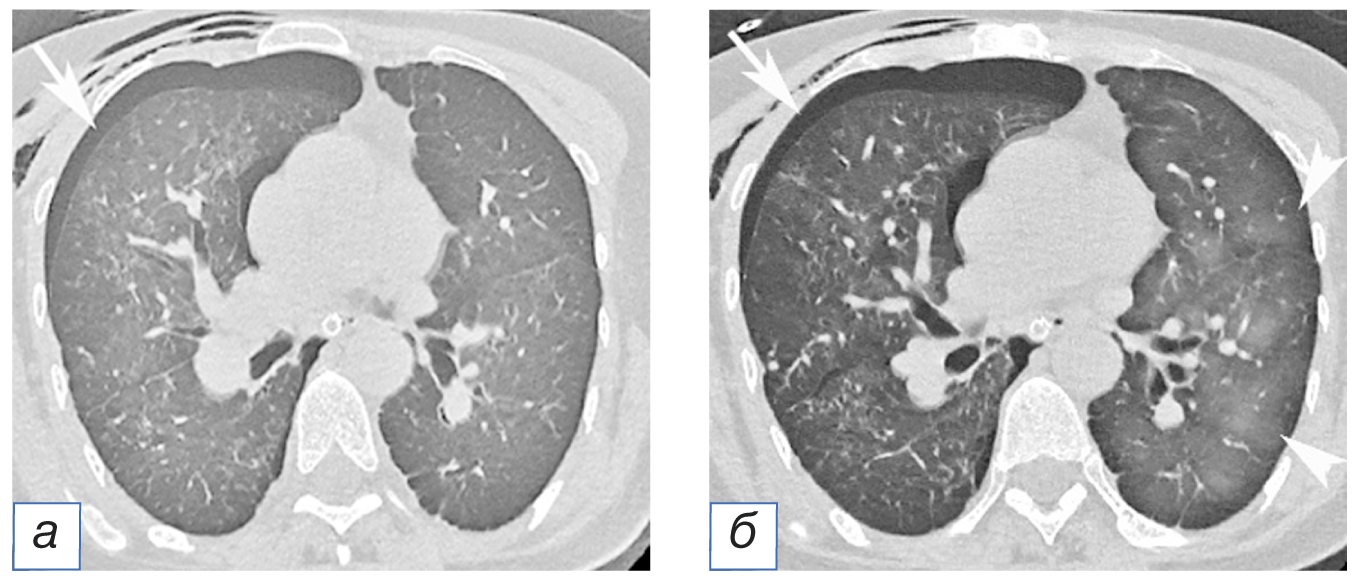

Результаты физикального, лабораторного и инструментального исследований. При рентгенографии и компьютерной томографии грудной клетки выявлен плевральный выпот, занимающий нижние, средние и частично верхние поля левого лёгкого, ателектаз нижней доли левого лёгкого (рис. 1, 2, а).

Рис. 1. Пациентка К., 38 лет. Рентгенограмма грудной полости: субтотальное затенение левой половины грудной клетки до уровня переднего отрезка II ребра слева, обусловленное плевральным выпотом (стрелка).

Лечение. Установлен дренаж 12G по левой передней подмышечной линии в четвёртом межреберье. Через 1 час после удаления ~1,6 л серозно-геморрагической жидкости в подводный герметичный дренаж пациентку стали беспокоить приступы кашля, развились острая одышка и тахипноэ с десатурацией (SpO2) до 83% (при дыхании кислородом 5 л/мин через простую маску), сопровождаемые гипотензией и тахикардией. При компьютерной томографии грудной клетки выявлено понижение прозрачности левого лёгкого по типу матового стекла с множественными внутридольковыми участками «консолидации» (см. рис. 2, б).

Рис. 2. Пациентка К., 38 лет. Компьютерная томограмма грудной полости: а — выпот в плевральной полости (стрелка), коллабированная нижняя доля левого лёгкого (головка стрелки); б — через 1 час после дренирования плевральной полости: снижение прозрачности лёгочной ткани по типу матового стекла, участки консолидации в базальных отделах левого лёгкого, обусловленные реэкспансивным отёком (стрелка).